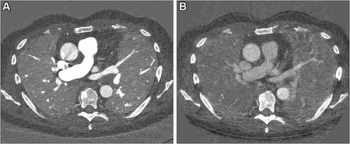

In a study of over 20,700 people, researchers found that artificial intelligence (AI) analysis of body composition measurements via lung cancer screening computed tomography (CT) exams improves the prediction of mortality risks for lung cancer, cardiovascular disease, and all-cause mortality.